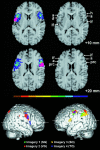

Broca's region in the dominant cerebral hemisphere is known to mediate the production of language but also contributes to comprehension. Here, we report the differential participation of Broca's region in imagery of motion in humans. Healthy volunteers were studied with functional magnetic resonance imaging (fMRI) while they imagined movement trajectories following different instructions. Imagery of right-hand finger movements induced a cortical activation pattern including dorsal and ventral portions of the premotor cortex, frontal medial wall areas, and cortical areas lining the intraparietal sulcus in both cerebral hemispheres. Imagery of movement observation and of a moving target specifically activated the opercular portion of the inferior frontal cortex. A left-hemispheric dominance was found for egocentric movements and a right-hemispheric dominance for movement characteristics in space. To precisely localize these inferior frontal activations, the fMRI data were coregistered with cytoarchitectonic maps of Broca's areas 44 and 45 in a common reference space. It was found that the activation areas in the opercular portion of the inferior frontal cortex were localized to area 44 of Broca's region. These activations of area 44 can be interpreted to possibly demonstrate the location of the human analogue to the so-called mirror neurones found in inferior frontal cortex of nonhuman primates. We suggest that area 44 mediates higher-order forelimb movement control resembling the neuronal mechanisms subserving speech.